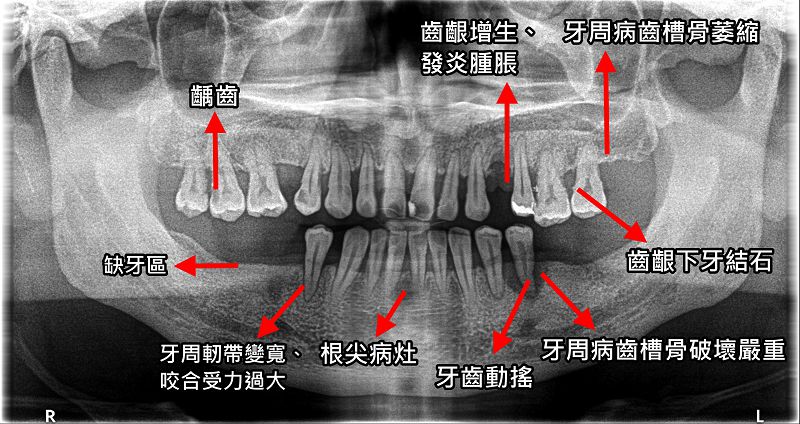

臺北榮民總醫院桃園分院牙科主任王碩表示,臨床上常見許多案例,因口腔問題未被及時處理,最終導致疾病惡化,患者除了飽受牙疼或發炎感染之苦,更因為已然病入膏肓,牙齒一顆顆逐漸鬆搖脫落,或不得已必須拔牙。然而有些口腔問題在初期時,患者常表示沒有不舒服,也無顯著症狀,加上未養成定期至醫療院所檢查口腔的習慣,極容易忽略口腔病況。以牙周疾病為例,許多患者往往都是等到牙齦出血嚴重、牙齦浮腫疼痛、牙齦萎縮過於明顯,甚至牙齒鬆動厲害時才尋求治療,但此時的牙周組織已經嚴重流失破壞,早已錯失了醫治的時機。

王碩主任並指出,假牙製作前的妥善治療,應包含口腔全面檢查,並針對欲做假牙位置及其鄰近區域,乃至於全頷或全口,完成必要的治療,除此之外,也應確保假牙復形區域的牙齒及周邊組織穩定,並提供患者完善的口腔清潔知識與衛教。如有齲齒、牙髓疾病等問題,應接受補牙、根管治療等處置;牙周病則應接受完整牙周治療療程,包含牙周囊袋與 X 光檢查、牙周基本治療與必要時之牙周翻瓣或補骨再生手術;口內的不良形態填補物也應去除並置換。王碩主任呼籲,患者除了接受專業臨床治療,同時應加強自我口腔清潔維護,以增加有救牙齒的保存機會與健康狀態。若是牙齒動搖或牙周組織破壞過於嚴重、齒源性感染嚴重,且經臨床專業評估確認已無法救治,也應考量於假牙製作前拔除,切莫以「再爛的牙都是自己的